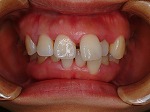

◆オールセラミック修復

~修復前~

オールセラミック修復

~修復後~

~修復後拡大~

~術前~

~術後~